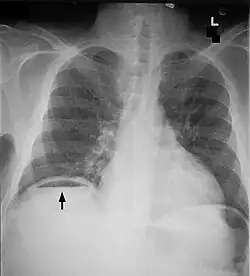

Free air under diaphragm seen on abdominal X-ray.

Abdominal free air

Bowel perforation presents with abdominal pain, free air in the abdomen on standing X-ray, and sepsis.[15][16][17] Depending on the cause and size, perforations may be medically or surgically managed. Some common causes of perforation are cancer, diverticulitis, and peptic ulcer disease.